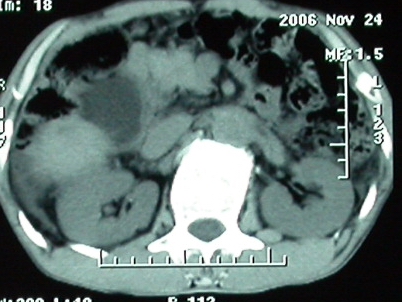

作者: rsyby 时间: 2006-11-28 22:53

增强ct所见

门脉主干及肠系膜上静脉近端明显增粗,尤其前者呈等低混杂密度,增强后周围见轻度环形强化。明显占位效应。肝内外胆管见大量气体影。胆囊明显增大。

考虑:1、门脉栓塞; 2、肝内外胆管积气。

ct表现:1,胰腺钩突后方肿块,不均强化,中心密度低,钩突及门静脉前移。2:肝右后叶不均强化灶,突出肝表面,3:胆囊明显增大,肝内胆管及肝总管内积气。4:腹腔内少量积液。

手术结果:

肝脏尾状叶肝癌(沿肝十二指肠韧带向下韧带内生长,门腔间隙外压增大),大结节性肝硬化,胆囊积脓,胆道感染。术中见肝外胆道2cm直径,肿瘤向前压迫胆管至扁平状态。